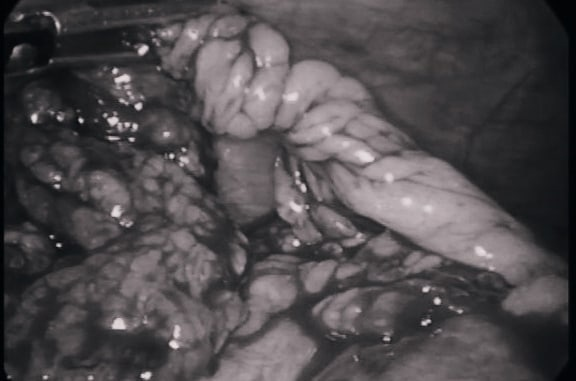

По информации источника, юного пациента доставили в больницу с подозрением на острый аппендицит. Однако уже во время операции выяснилось, что у ребенка перекрут и некроз пряди большого сальника. Отмечается, что данное заболевание встречается у больных с острой хирургической патологией органов брюшной полости лишь в 0,09–0,3% случаев.

Врачи провели лапороскопическую операцию и удалили часть сальника. Сейчас ребенка уже выписали из больницы.